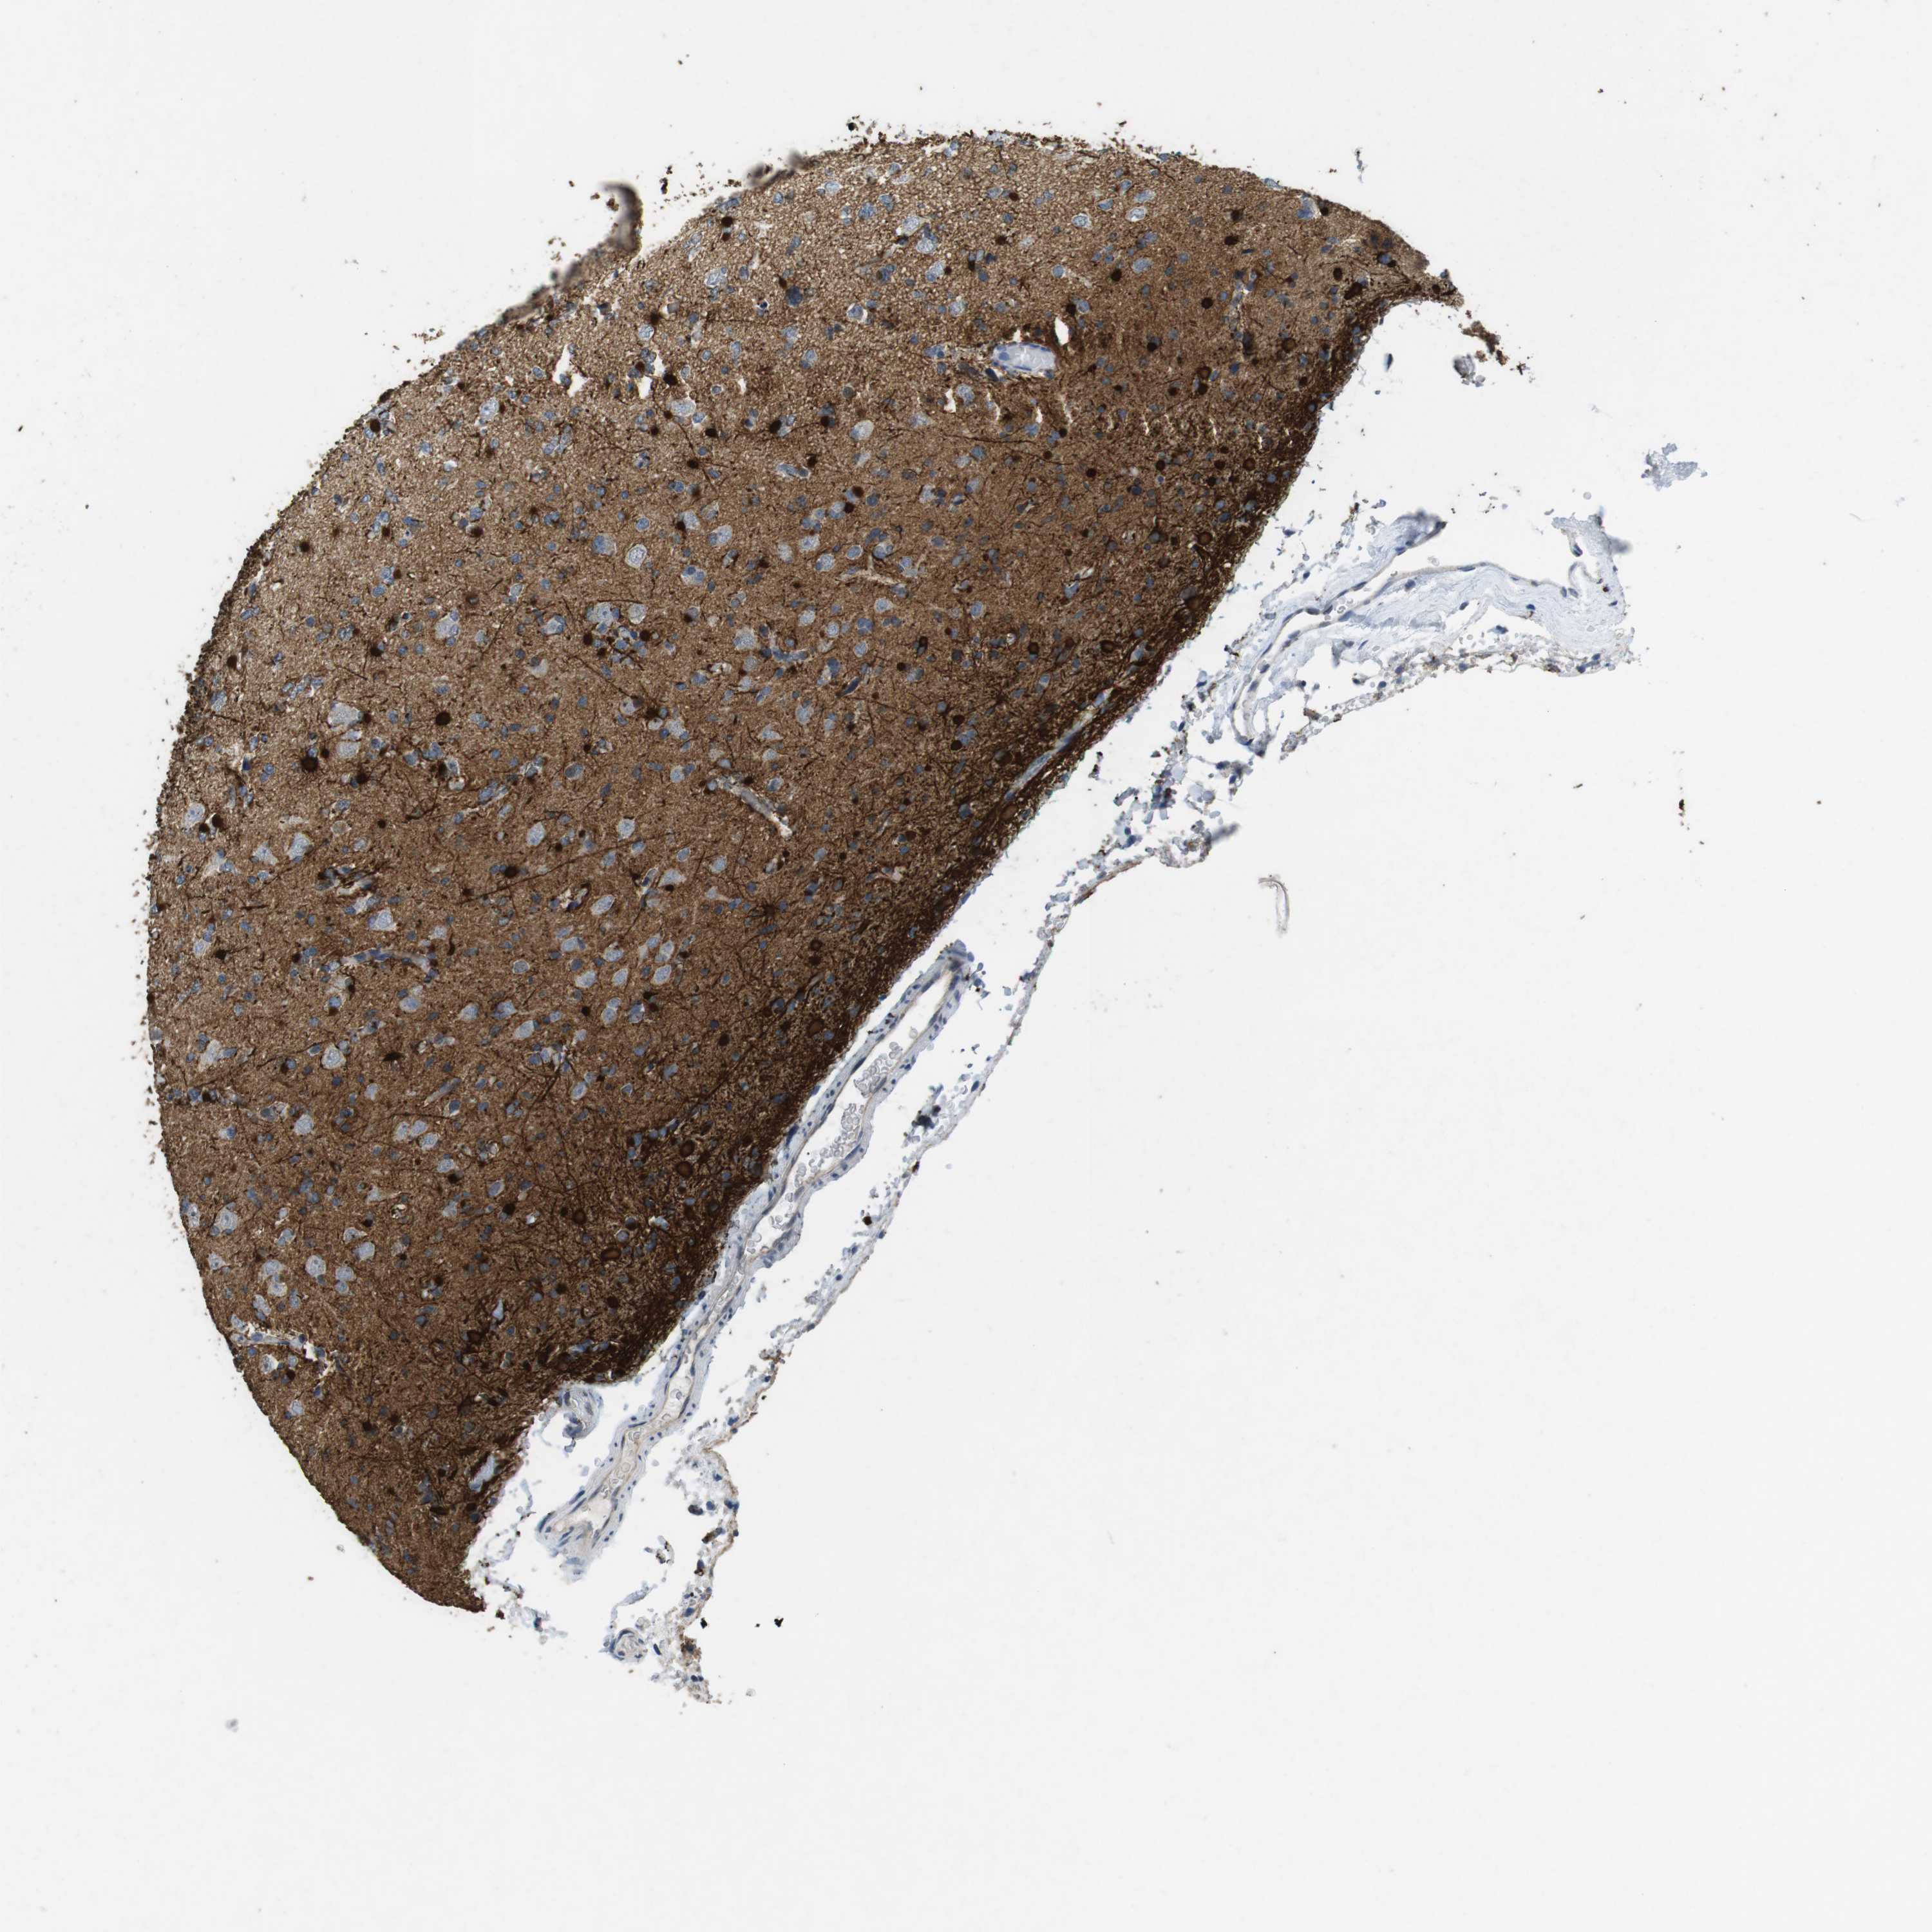

GLIOMA - Protein expressioni

A mouse-over function shows sample information and annotation data. Click on an image to view it in a full screen mode. Samples can be filtered based on level of antibody staining by selecting one or several of the following categories: high, medium, low and not detected. The assay and annotation is described here.

Note that samples used for immunohistochemistry by the Human Protein Atlas do not correspond to samples in the TCGA dataset.

Antibody stainingi

Antibody staining in the annotated cell types in the current human tissue is reported as not detected, low, medium, or high, based on conventional immunohistochemistry profiling in selected tissues. This score is based on the combination of the staining intensity and fraction of stained cells.

Each image is clickable and will lead to virtual microscopy that enables deeper exploration of all samples and also displays staining intensity scores, fraction scores and subcellular localization as well as patient and tissue information for each sample.

Antibody HPA026846

Antibody CAB016135

Staining

High

Medium

Low

Not detected

Intensity

Strong

Moderate

Weak

Negative

Quantity

>75%

75%-25%

<25%

None

Location

Nuclear

Cytoplasmic/membranous

Cytoplasmic/membranous,nuclear

Glioma, malignant, High grade

Glioma, malignant, Low grade